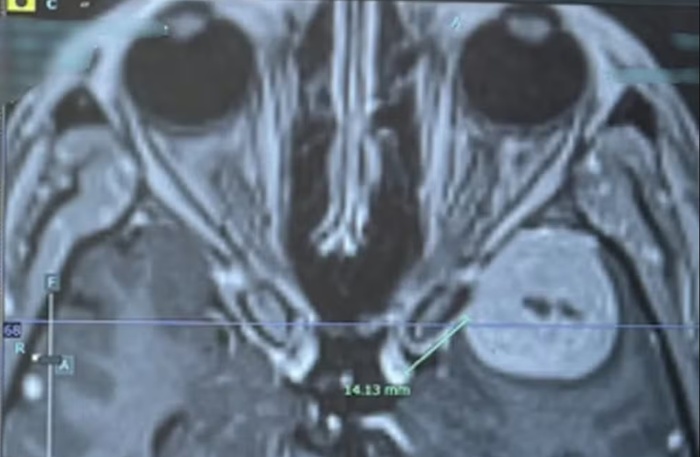

Os médicos disseram ter encontrado algo preocupante e a encaminharam para o The Grange, em Cwmbran, onde ela passou por uma ressonância magnética. A moradora de Hereford, na Inglaterra, descobriu um tumor do tamanho de uma bola de golfe, chamado meningioma, no cérebro.

Em maio, ela passou por uma cirurgia para remover o tumor, que já havia crescido mais e estava a apenas três milímetros de seu nervo óptico, podendo deixá-la cega.